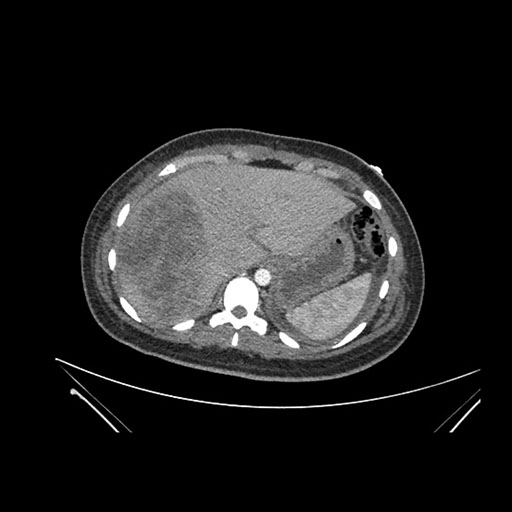

Axial Arterial

Imaging analysis

Based on initial findings, which issue(s) would you be most concerned about?